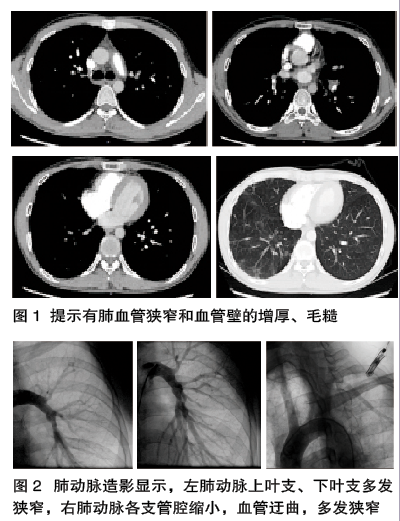

综合分析,年轻男性,反复胸痛、咯血,逐渐出现呼吸困难,肺部听诊闻及血管杂音,CRP、ESR等炎性指标升高,HLA中B51阳性,CTPA提示有肺血管狭窄和血管壁的增厚、毛糙(图1),肺动脉造影提示多处的肺动脉狭窄、迂曲(图2),均支持大动脉炎,考虑大动脉炎肺血管型。

完善检查: HLA-B51阳性。右心导管+肺动脉+大动脉主要分支造影:左肺动脉上叶支、下叶支多发狭窄,右肺动脉各支管腔缩小,血管迂曲,多发狭窄。平均肺动脉动脉压30 mmHg。